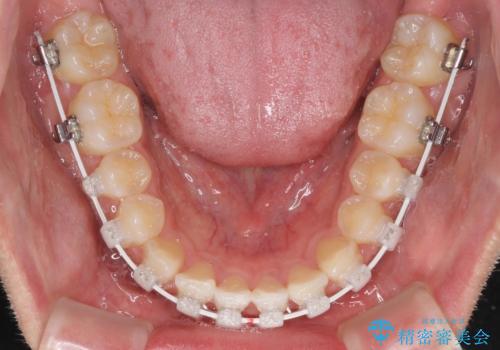

治療期間を極力短くしたいとのことで、ワイヤー矯正により治療を行うこととしました。

今後はすり減ってしまった歯の形をセラミッククラウンで改善したいとのことで、クロスバイトが改善し咬みやすくなった時点で装置を外すこととしました。